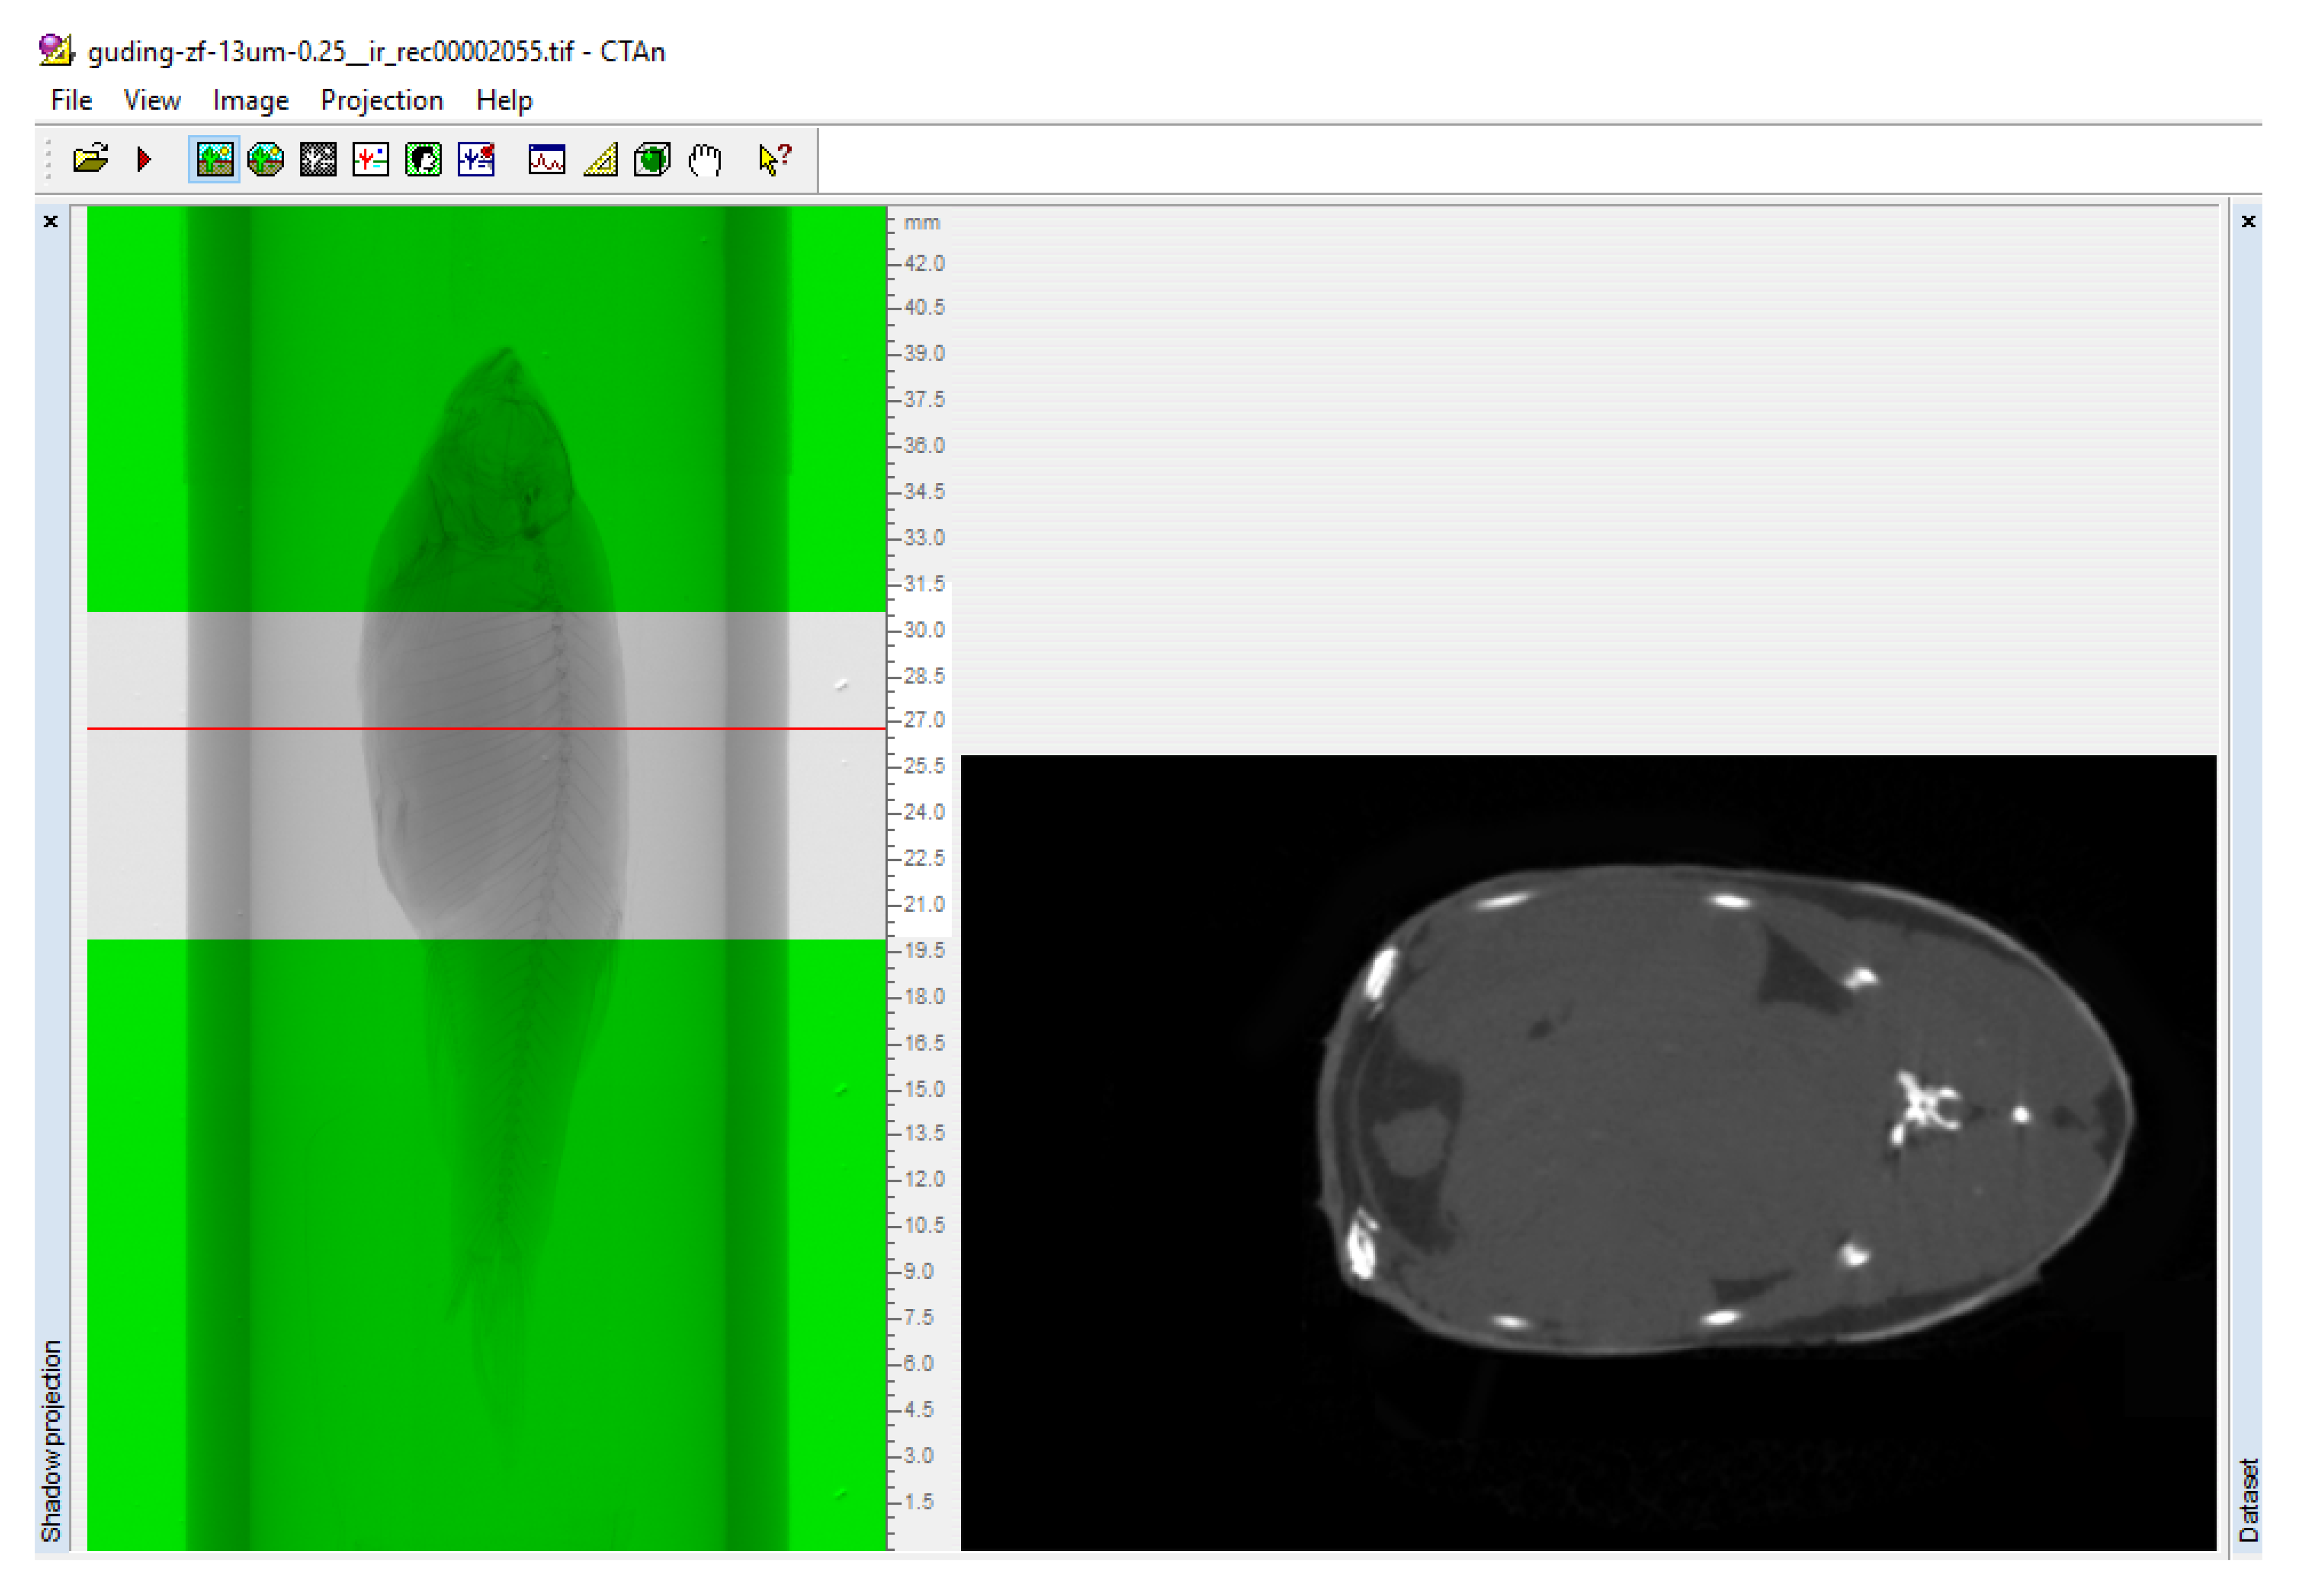

2.5. Data Processing

3.1. Method to Detect Adipose Tissue in Zebrafish by CT Scanning

3.3. Scanning the Standard Plane of Trunk Adipose Tissue